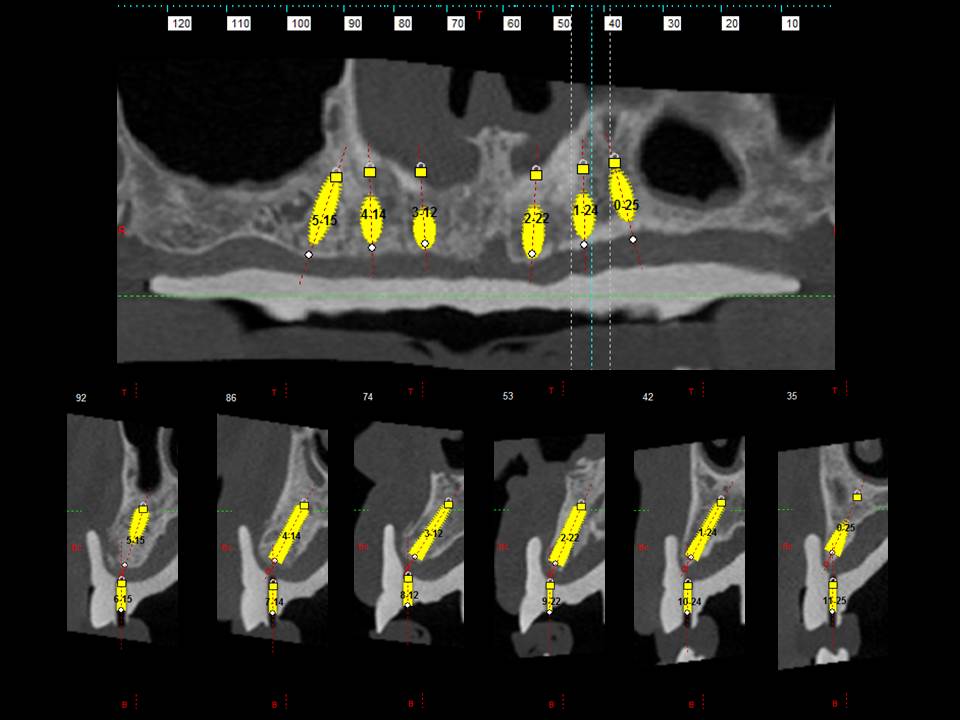

Prótesis fija OT BRIDGE

E - BOOK y CASOS CLÍNICOS

CASOS CLÍNICOS